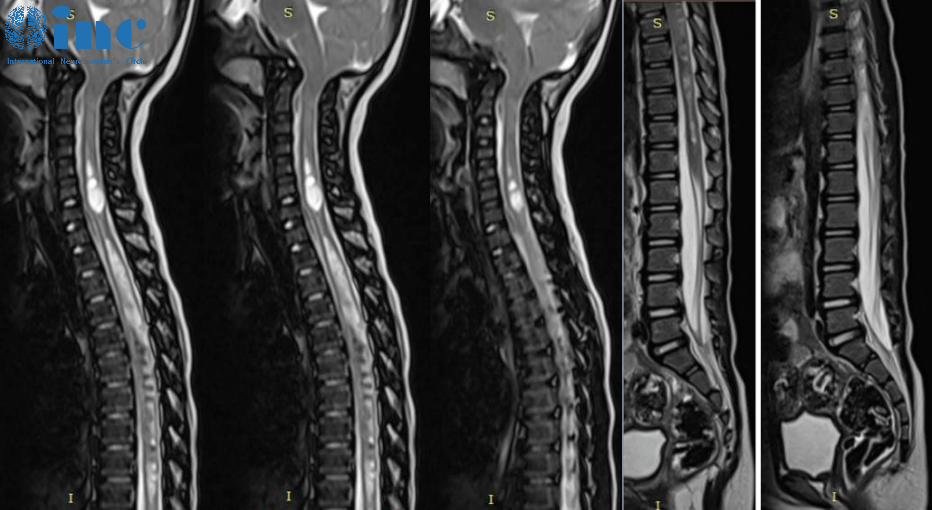

2022年1月初进行的全脑和脊髓MRI检查显示小脑蚓部和扁桃体疝以及脊髓空洞腔,从C4到T11更明显(但也涉及到了脊髓的较尾部),没有任何明显的脊髓栓系的证据。

小脑结构的下降几乎完全闭塞了脑池的空间,明显干扰颅脊交界处的脑脊液循环。

CT重建提示颅脑比例失调,这是因为大脑凸面的蛛网膜下腔体积减小,小脑蚓部向上迁移,以及与小脑中度过度生长相关的小脑幕的向上移位。

尽管脊柱MR没有证实脊髓的栓系,但在圆锥体位置正常甚高于正常位置的儿童中曾报道终丝牵拉征。考虑到这方面,Di Rocco教授建议涛涛躺在俯卧的体位下再重复脊柱MRI检查可能是有用的。